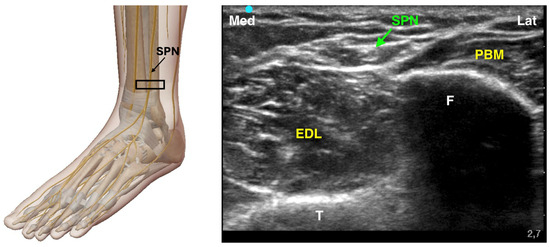

4.3.3. Superficial Peroneal Nerve Block

The superficial peroneal nerve provides sensory innervation to most of the dorsum of the foot. It originates from the common peroneal nerve and runs subcutaneously in the distal third of the leg. Due to its highly variable branching pattern, ultrasound guidance is recommended to increase the accuracy of the block. The SPN travels deep to the muscular fascia, positioned between the extensor digitorum longus (EDL) anteriorly and the fibularis longus (FL) and fibularis brevis (FB) posteriorly. As it descends, the SPN pierces the muscular fascia to divide into its terminal branches, which supply sensory innervation to the dorsal aspect of the foot. To perform an ultrasound-guided SPN block, the probe is typically placed proximal to the lateral malleolus and scanned cephalad along the fibula with the patient in a supine position. The nerve can be identified as it crosses the muscular fascia, distinguishing the adjacent muscle groups (Figure 5). Dynamic scanning helps to trace the nerve’s course and confirm its location. A 25-gauge needle is then advanced, and 3–5 mL of local anesthetic is injected either superficial or deep to the muscular fascia. Since the SPN may branch before fully emerging through the fascia, the block should be performed at an appropriate level to ensure an effective sensory blockade of the foot [19,27].

Figure 5. Ultrasound-guided Superficial Peroneal Nerve Block. SPN: Superficial Peroneal Nerve; F: Fibula; T: Tibia; EDL: Extensor Digitorum Longus Muscle; PBM: Peroneus Brevis Muscle; The black rectangle indicates the placement of the ultrasound probe on the anatomical area.